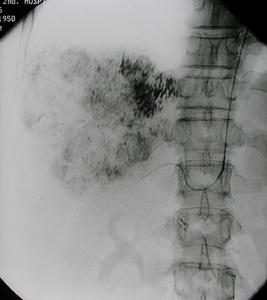

④ 動脈造影:能準確顯示病變的部位、範圍,程度、側支和閉塞遠側動脈主幹的情況,對選擇手術方法有重要意義。磁共振血管造影(MRA)和數字減影血管造影(DSA)都能達到診斷和指導治療的目的。動脈硬化性閉塞症與血栓閉塞性脈管炎的症狀相似,需作鑑別診斷;此外,還應與大動脈炎、動脈栓塞等相鑑別。

(四)動脈造影以明確栓塞部位、範圍及程度 。